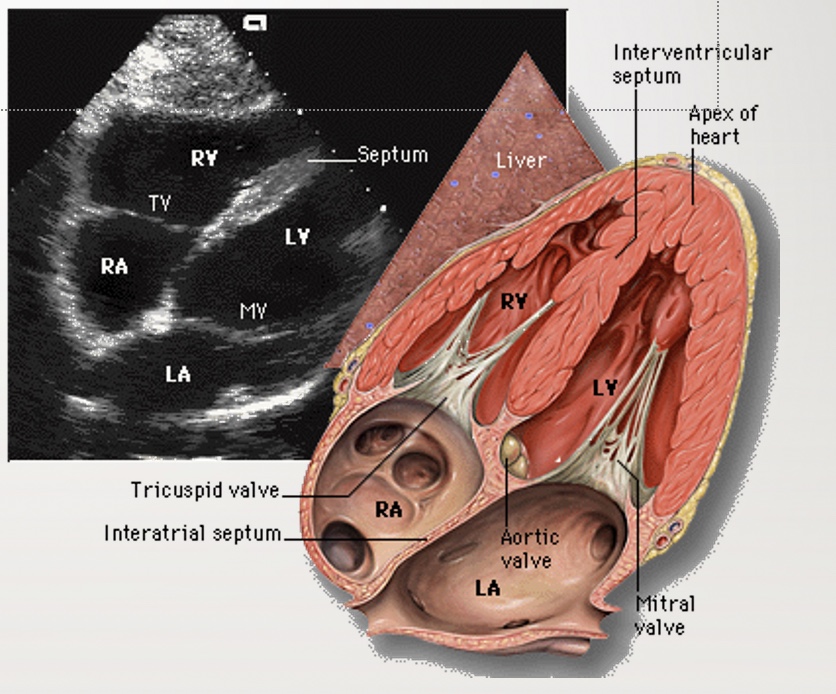

Identify the view and structures

Apical 4 chamber